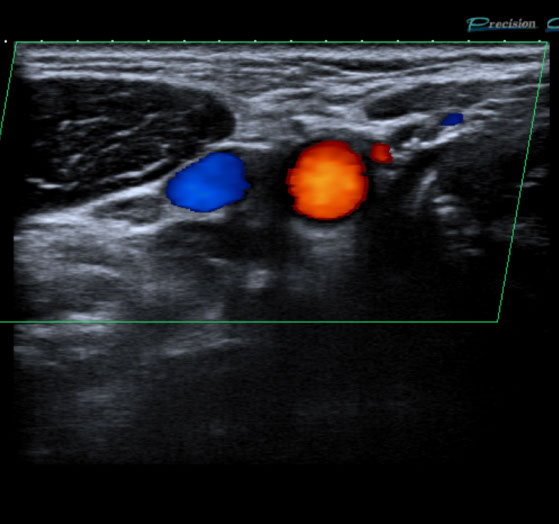

Gefäßultraschall /

Farbdopplersonographie

Die Farbdopplersonographie ist eine zuverlässige Methode zur Beurteilung von Arterien und Venen. Die Farbdopplersonographie kann einerseits Veränderungen der Gefäßwände (z.B. arteriosklerotische Plaques) und dadurch resultierende Engstellen (Stenosen) nachweisen, andererseits durch Blutflussgeschwindigkeitsmessungen den Schweregrad der Stenosen beurteilen. Risikofaktoren für Arteriosklerose und damit für Schlaganfall und Herzinfarkt sind z.B. erhöhte Blutfettwerte, hoher Blutdruck (Hypertonus), Nikotinkonsum.